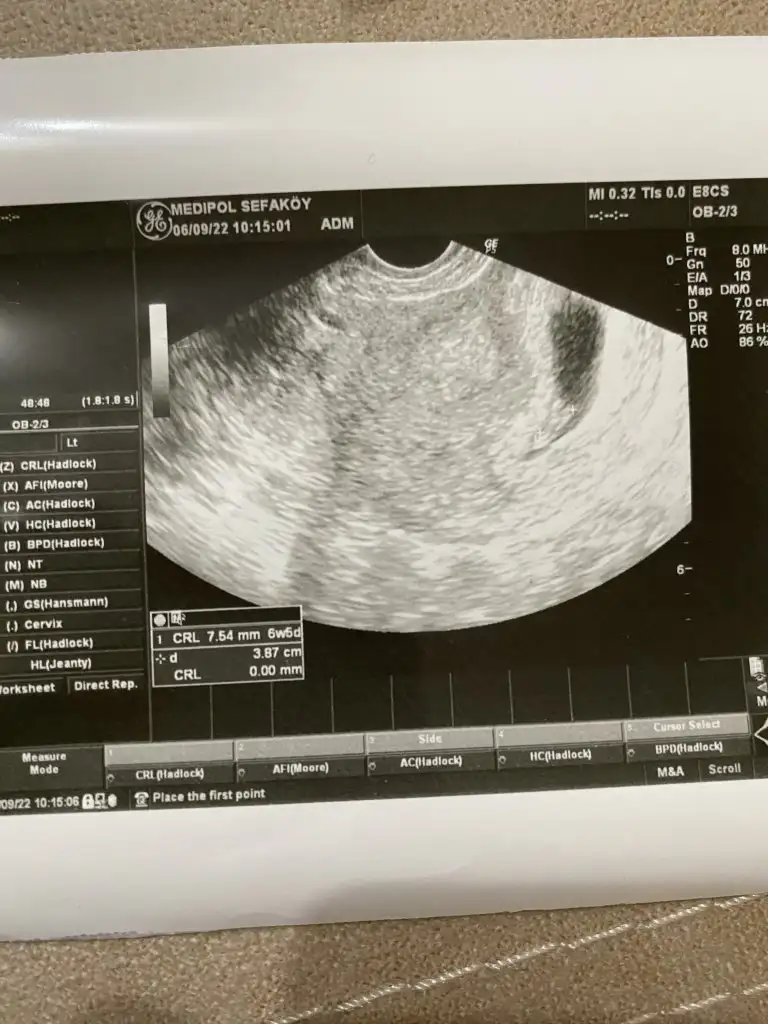

Ay çok şükür canım gözün aydınKızlar dayanamadım çarşamba sabahı bekleyemedim. Geçen hafta gittiğim doktor bugün nöbetçiydi. Hazır dışardayken ona da uğrayayım dedimKarından baktı iyi göremedi. Vajinal baktı çok şükür bebeği gördük. Birkaç saniye kalp atışını da duyduk. Progestana devam et 1 ay sonra tetkiklerini yaptırıp gel dedi. Her şey iyi duruyor dedi çok şükür. 7+1’im ama CRL’ye göre 6+5 çıktım o da normal heralde. Şimdi ben ramziye göre yorumlanabilirim değil mi

Sanki kesenin solunda gibi görünüyo, Ramziye göre erkek oluyo bu durumda ama vajinal bakılmış o zaman tersi olur, yani kız olabilir bu bebiş